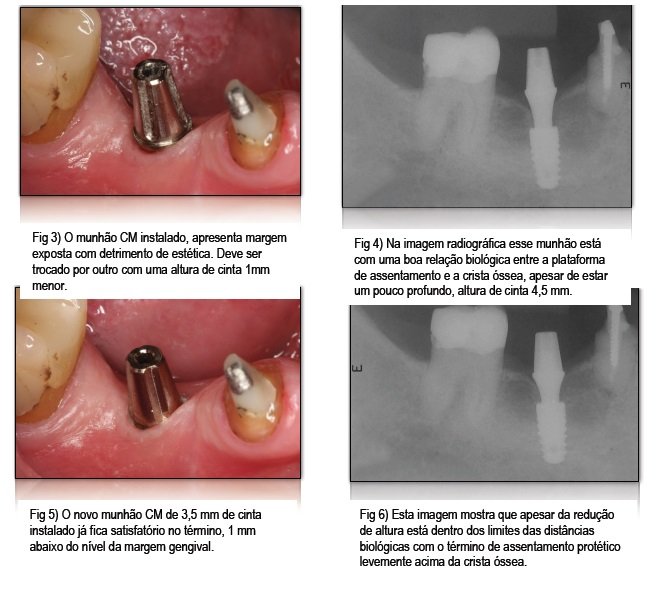

3) Para preservação óssea marginal ao redor dos implantes, a base de assentamento protético do munhão deve estar de 1 a 1,5 mm acima da crista.

4) Para melhor estética, a base se assentamento protético deve ficar de 1 a 2mm abaixo da margem gengival aparente.